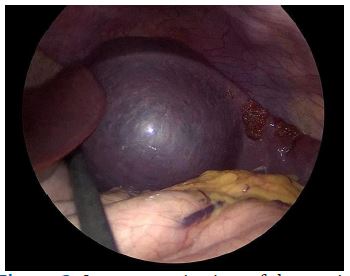

We scheduled a multidisciplinary discussion with surgeons, radiologists and paediatricians and decided to manage the cystic lesion by laparoscopic partial splenectomy with ultrasound guidance. The patient had been previously vaccinated for encapsulated bacteria and was prescribed perioperative antibiotic prophylaxis with cefazoline and anti-thromboembolic prophylaxis with enoxaparin. The operation was performed under general anaesthesia. The patient was placed in a supine position on the operative table and we placed four trocars (three 5 mm trocar and one 15 mm trocar) as described in previous works [6]. The exploration of the abdomen showed a cystic lesion of the upper pole of the spleen (Figure 3). IOUS was performed, marking the margins of the lesion and confirming the absence of further cysts. After division of the gastrosplenic ligament and mobilization of the posterior spleen’s attachments, we emptied the cystic lesion with a needle and collected about 50 ml of clear fluid. We coagulated the feeding vessels with a radiofrequency device (LigaSure™ Medtronic) keeping a 1 cm distance from the margin of the lesion as identified with IOUS until we obtained an ischemic demarcation of the splenic parenchyma. The transection of the parenchyma was then performed, under IOUS guidance, using the radiofrequency device. A bipolar coagulation device (Aquamantys™ bipolar sealers Medtronic) was used for haemostasis (Figure 4). The residual spleen was estimated to be about a third of the entire initial splenic volume (Figure 5). A laparoscopic stitch was placed in order to fix the remaining spleen to the omentum and avoid a possible torsion of the pedicle’s vessels and subsequent ischaemia of the residual organ.

Figure 3: Laparoscopic view of the cystic lymphangioma ot the upper splenic pole.